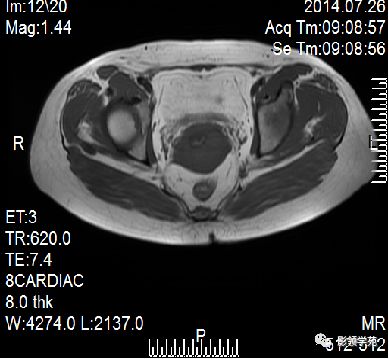

宫颈癌MRI表现

宫颈癌可表现为类圆形或不规则形肿块,在T2WI上表现为均匀或欠均匀的高信号,与正常宫颈基质及宫旁脂肪形成良好的自然对比。

MRI

- Ⅰ期肿瘤:侵犯宫颈基质,T2WI等信号肿块,宫颈管扩大及宫颈纤维基质中断

- Ⅱ期肿瘤:宫颈增大,宫旁肿块或宫旁脂肪组织内出现异常信号的粗线状影

- Ⅲ期肿瘤:侵犯至阴道下部,外延至盆壁,或出现肾积水。

- Ⅳ期肿瘤:膀胱壁或直肠壁低信号中断,膀胱壁或直肠壁增厚或腔内肿块。

DWI:局限性高信号,癌组织ADC值<癌旁组织<小于正常宫颈组织